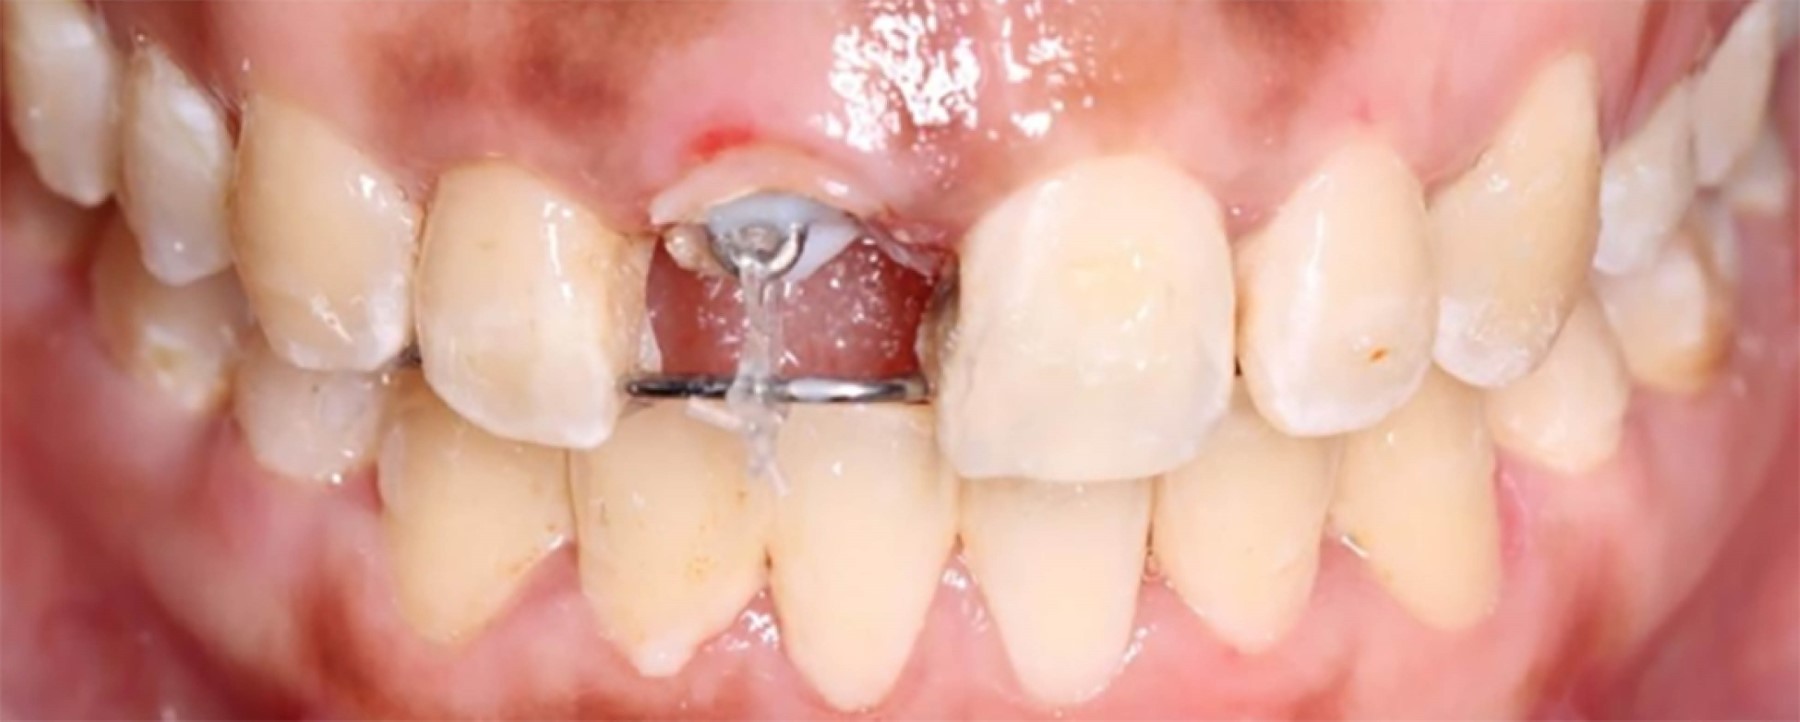

Una vez analizado el caso, se decide realizar la técnica de extrusión forzada rápida del órgano dental 1.1. Se realizó raspado coronal e instalación de la aparatología, la cual está constituida por un alambre de ortodoncia #36 adaptado y cementado con resina por caras linguales de piezas 1.3, 1.2, 1.1, 2.1 y 1.2, además de la formación de un loop del mismo alambre y cementado de manera provisional en el interior del conducto. Adicionalmente, se colocó cadenas elastoméricas de segunda generación del loop hacia el alambre en área de pieza 1 (Figura 2).

Figura 2